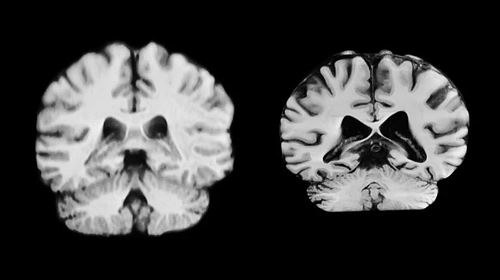

针对大脑皮层扩张,学术界曾有两大假说:一派认为源于海马和梨状皮层等古老异皮层,另一派主张从初级感觉皮层向外扩张。审稿人评价,这项原创突破为理解大脑演化奥秘提供了全新视角,将对神经生物学及多学科领域产生深远影响。